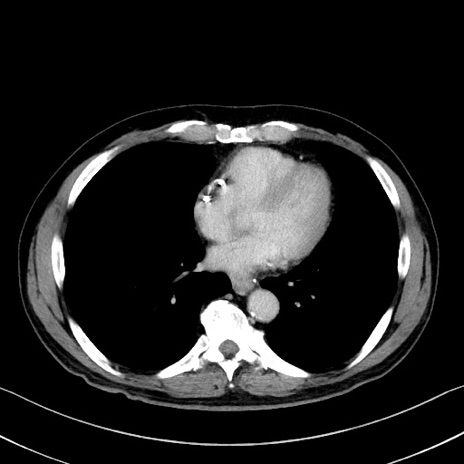

症例35(横断像)

【症例】70歳代 男性

【主訴】腹部膨満、嘔吐

【現病歴】昨日より腹部膨満感出現。本日増悪し、仙痛出現。嘔吐あり、受診。

【既往歴】糖尿病、胆摘後

【身体所見】BP 149/80mmHg、HR 74/min、BT 35.9℃、腹部:膨満、軟、圧痛なし。腸雑音減弱あり。上腹部正中切開瘢痕あり。

【データ】WBC 13500、CRP 1.72